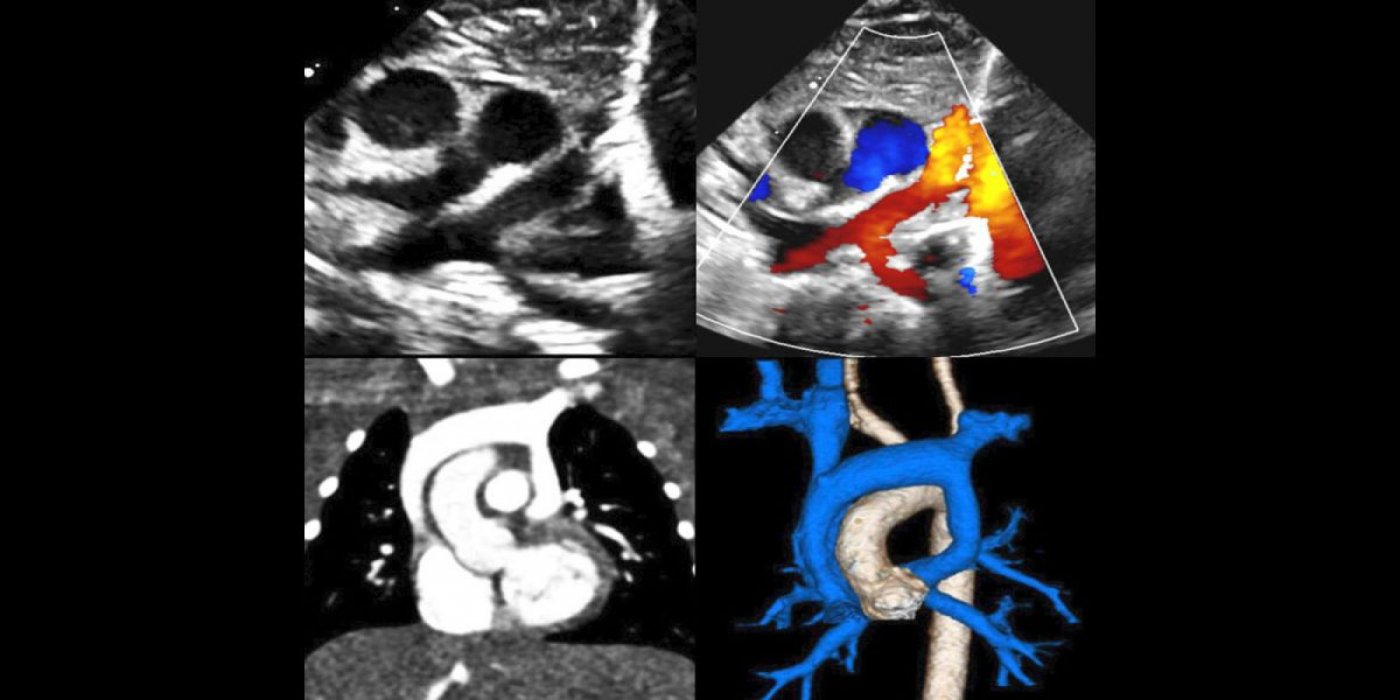

This three-day symposium is designed to provide a deeper understanding of the anatomy, clinical aspects, imaging, and management of patients with congenital heart disease. The symposium will include case discussions, didactic seminars, anatomic and imaging correlations, and discussions of multimodal imaging to illustrate the impact of cardiac imaging on treatment, diagnosis, and management of patients with congenital heart disease.